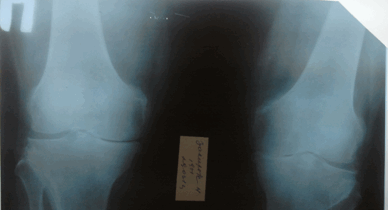

(Слева) Рентгенография в ПЗ проекции: ОА латерального отдела коленною сустава ва. На фоне вальгусной деформации визуализируются остеофиты и определяется полная утрата хряща. Несмотря на то, что поражение медиального отдела считается типичным при ОА, поражение латеральною отдела может доминировать.

(Справа) Рентгенография в ПЗ проекции: пример раннею ОА, характеризующегося исключительно формированием остеофитов. При рентгенографии, выполненной с осевой нагрузкой, признаки нарушения соосности и утраты хряща не определяются. Остеофиты визуализируются только в области межмыщелковго возвышения большеберцовой кости. (Слева) Рентгенография в боковой проекции, этот же пациент: определяются остеофиты надколенника. Также визуализируется субхондральный остеофит поверхности мыщелка бедренной кости. Субхондральные остеофиты часто сопровождаются фокальным дефектом хряща, что в этом случае подтвердилось при МРТ. Обратите внимание на отсутствие свободных тел.

Потерю хряща на рентгенограмме оценивали с помощью измерения ширины суставной щели. На МРТ непосредственно измеряли высоту суставного хряща. Потеря хряща на рентгенограмме была выявлена в медиальном отделе в 57(85 %), в латеральном отделе в 23(34.3 %), на МРТ в 63(94 %) и 40(59.7 %) суставах соответственно.

Остеофиты на рентгенограмме и на МРТ выявляли как краевые приострения суставных поверхностей костей(рис.1). Остеофиты на рентгенограмме были выявлены в медиальном и латеральном отделах в 40(59.7 %), на МРТ в 67(100 %) и 57(85 %) суставах соответственно.

Рис. 1. Рентгенограмма и МРТ коленных суставов больной З.,62 лет. На рентгенограмме (А) выраженное сужение медиальных отделов суставной щели, краевые остеофиты, субхондральный склероз. На МРТ(Б) краевые приострения, выраженные дегегнеративные изменения в медиальных отделов субхондральной кости, выраженное истончение медиального отдела хряща. Дегенерация медиального мениска